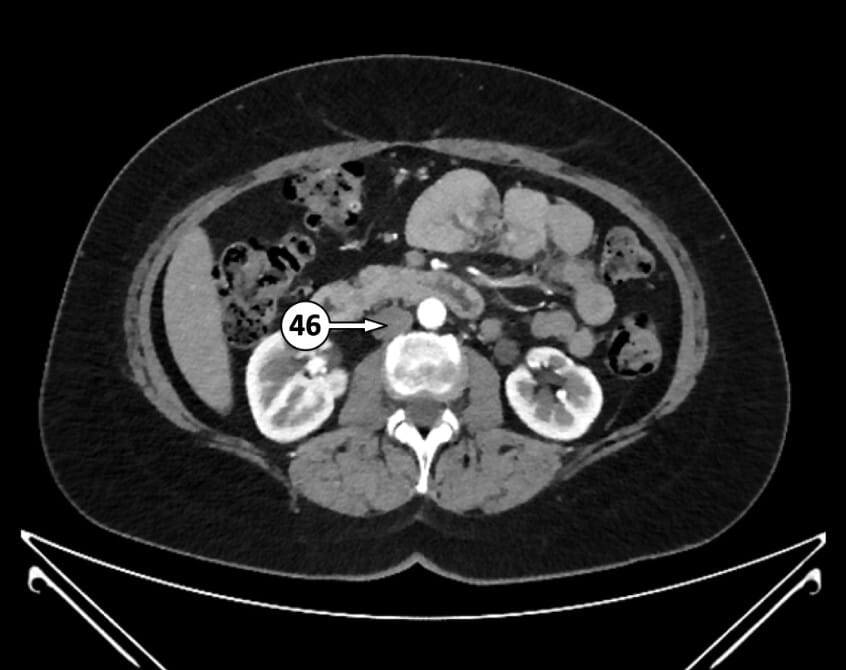

46. infrarenal segment of inferior vena cava